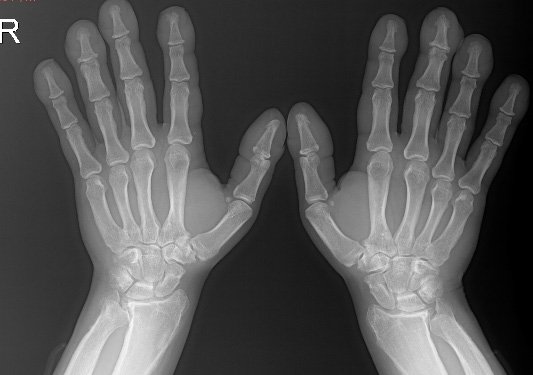

A 26-year-old male presented to the outpatient clinic because of expansion of his hands and feet since the age of 12 (Figure 1). With widespread pain and swelling in both ankles and knees. Expansion of his hands was insidious in onset and associated with excessive sweating. Positive family history of same complaint in milder degree in his father and elder sister. He had another healthy sister and brother. There was a kinship between the patient's parents. In physical examination, there was severe clubbing of all fingers and toes with enlarged distal extremities. The skin of both hands and feet was thickened. He had arthritis in both knees and ankles. X-ray images showed hypertrophic osteoarthropathy and acroosteolysis (Figure 2). We confirmed the synovitis by magnetic resonance imaging of the knee. Complete blood count, serum glucose, alkaline phosphatase, calcium and phosphorous were normal. Serum growth hormone (GH), insulin-like growth factor 1 (IGF1), thyroid stimulating hormone, free thyroxine 4, prolactin, testosterone, adrenocorticotrophic hormone, and cortisol were normal. Sedimentation rate (ESR) and C - reactive protein were found to be high (104mm/h, 21mg/L, respectively). The patient was diagnosed as pachydermoperiostosis after exclusion of excessive GH production. Treatment including colchicine, acemetacin, and biphosphonate was initiated. Arthritis was improved dramatically, and remarkably patient's symptoms were calm down in a short period.

Figure 2 X-ray images showed hypertrophic osteoarthropathy and acroosteolysis.